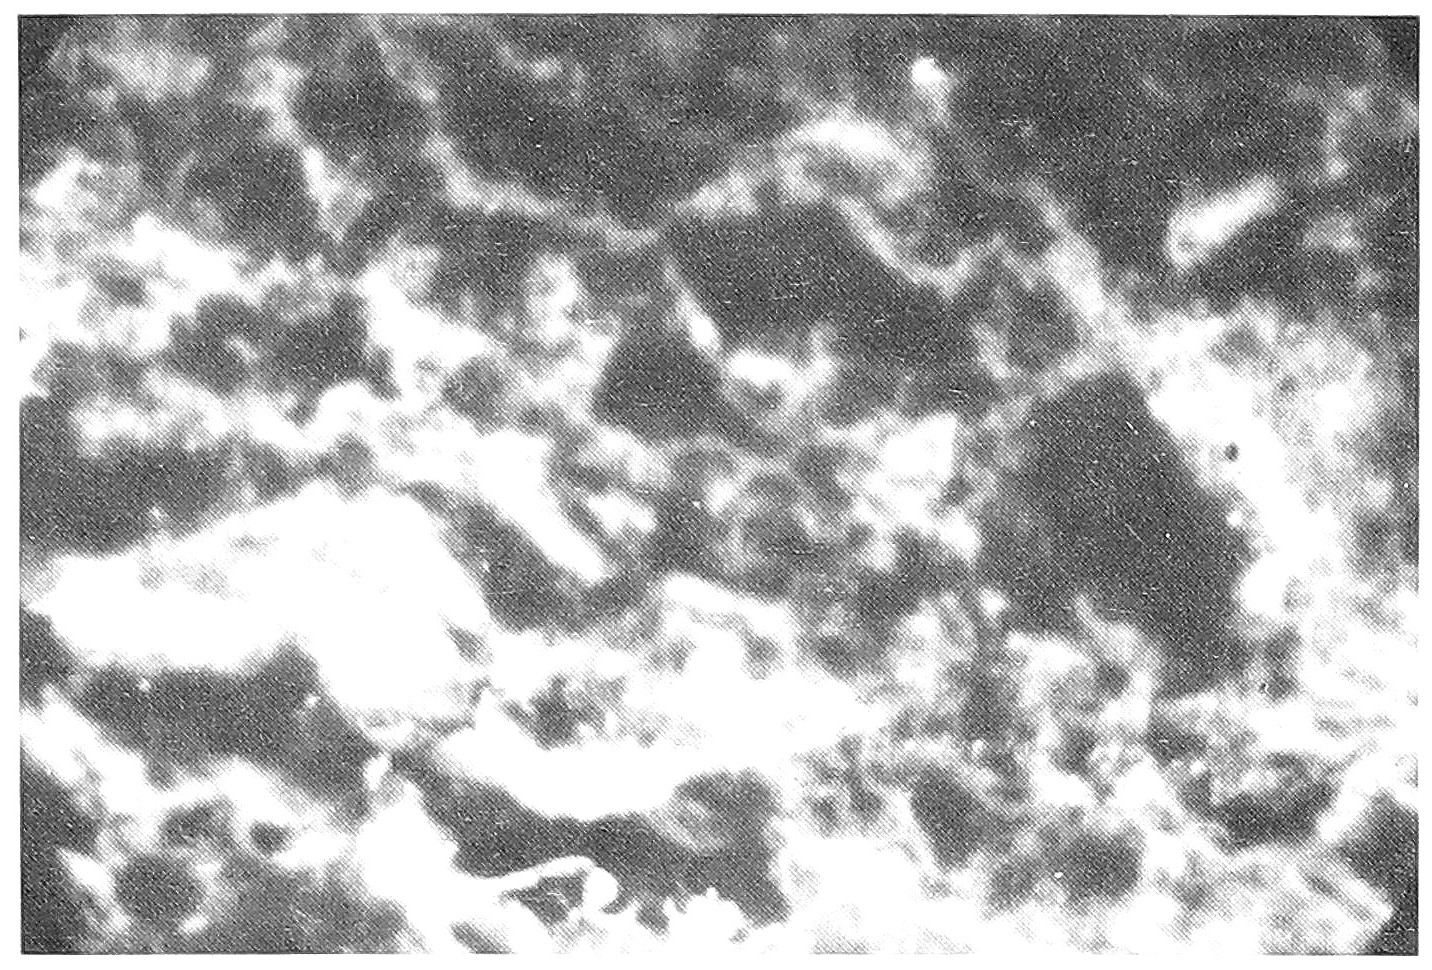

Из 29 перинатально погибших плодов и новорожденных было 7 (24,1%) с аномалиями развития. 3 из них погибли интранатально, 3 - сразу после родов и 1 - антенатально. Из 7 у трех были множественные пороки развития. У 1 - аномалия пупочного канатика, у 1 - волчья пасть и заячья губа, у 1 - врожденный порок сердца и у 1 аномалия развития почек. Все женщины, родившие детей с множественными пороками, перенесли ОРВИ до 5 нед. беременности. У всех трех в плаценте и органах плода выделен антиген гриппа A (H1N1). Мать ребенка, родившегося с волчьей пастью и заячьей губой, ОРВИ перенесла в 5 нед. и затем еще многократно при беременности. В плаценте и печени ребенка выделен антиген А (H1N1), в легких и мозге - A (H1N1) и PC. И в плаценте, и мозге ребенка с врожденным пороком сердца выделен антиген АД, а из печени АД + А (H1Nl) (pиc. 1,2, 3,4).

Рис. 2. Специфическое свечение антигена гриппа A (H2N2) в легких, ув. 200.